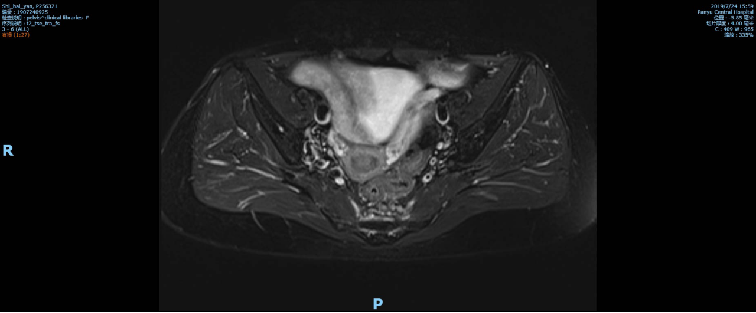

2019-09-09复查盆腔MR示直肠全段管壁不均匀增厚,以中段较明显,最厚处约12mm,较前改善,仍考虑累及浆膜面,不除外直肠前筋膜受累。

放化疗后影像学: